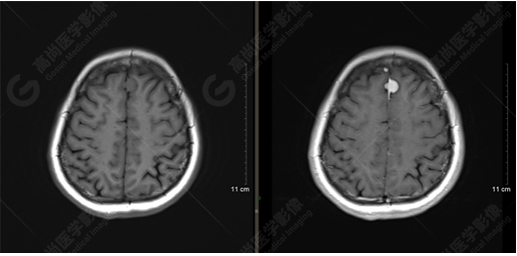

T1WI及T1增強(qiáng)序列